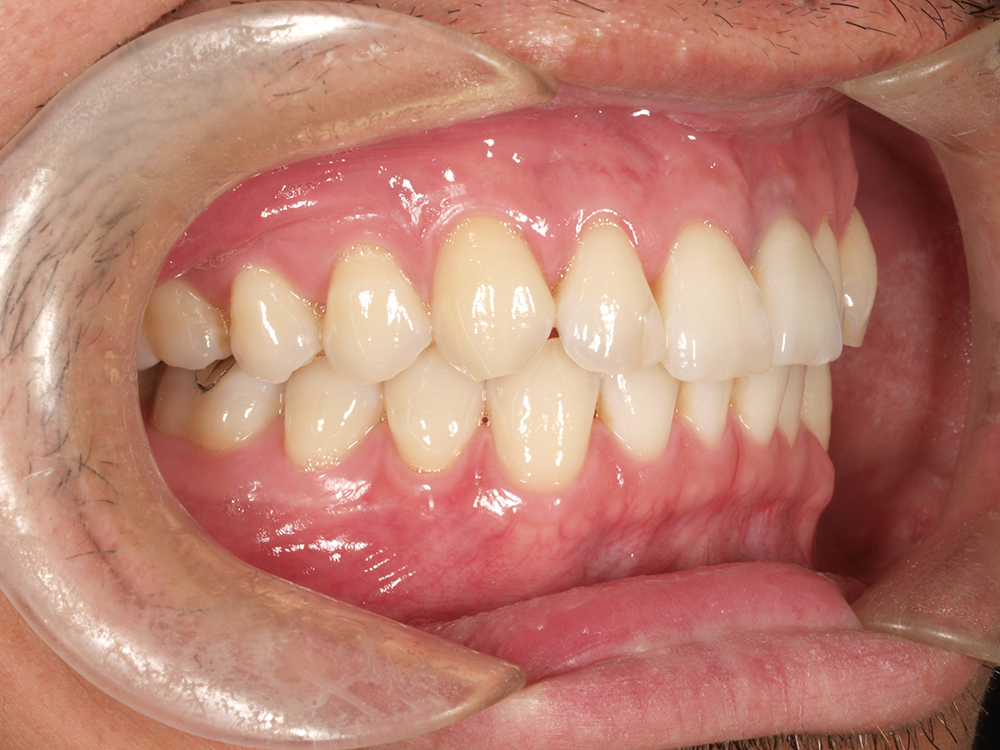

45歳 男性 医療関係者紹介

- 主訴

- 右前歯が取れた(右上2)

- 処置内容

1本インプラント埋入+再生療法

抜歯即時埋入⇒抜歯を行い、同時にインプラント埋入(即時埋入)

- 治療費用

- 上顎:約40万円(税込)

- 治療期間

- 約11か月

- リスク

- 上部構造物、仮歯の破折、術後の腫れ(3日)、人工歯根脱落リスクがあります